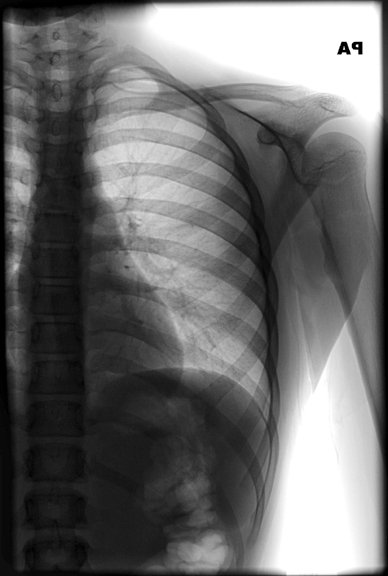

Identify the transverse process of 1st thoracic vertebra and 1st rib. Click the image for labeling.